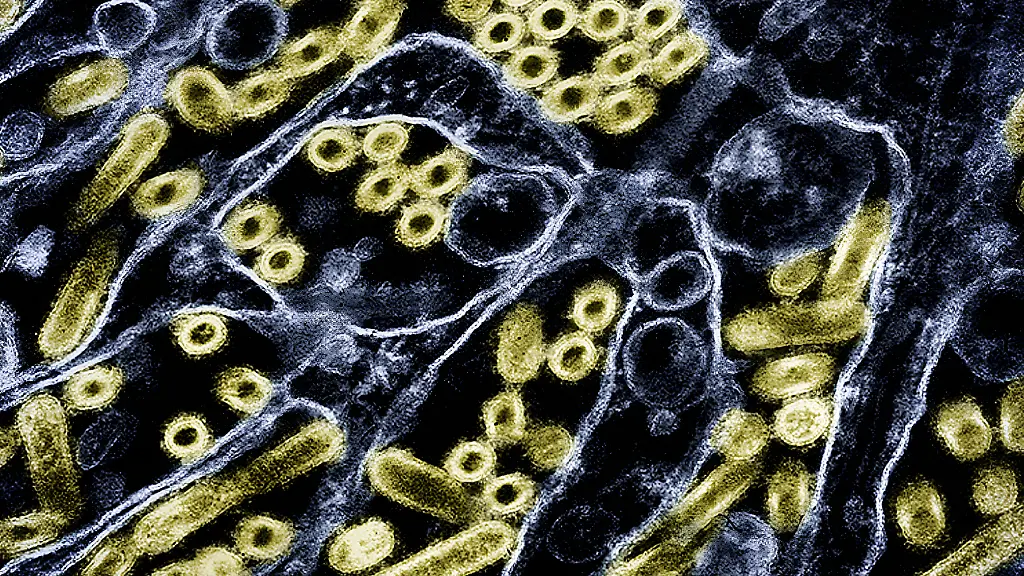

Nur eine Mutation entferntIst das Vogelgrippe-Virus kurz vor Anpassung an Menschen?

In den USA grassiert das Vogelgrippe-Virus H5N1 inzwischen auf Rinderfarmen. Forscher finden nun heraus, dass eine einzige Mutation beim Virus ausreichen könnte, damit es Menschen leichter infiziert. Eine große Sorge ist, dass dies eine neue Pandemie zur Folge haben könnte.

Das Vogelgrippe-Virus H5N1 grassiert seit einigen Monaten in Geflügelbetrieben sowie in Milchbetrieben in den USA - und schürt die Angst vor einer neuen Pandemie. Mehr als 50 Infektionen bei Menschen wurden in den USA bereits festgestellt. Die meisten Menschen infizierten sich auf Milchviehbetrieben. Forscher finden nun heraus, dass eine einzelne Mutation beim Virus ausreichen könnte, um eine Ansteckung mit dem Erreger bei Menschen zu erleichtern.